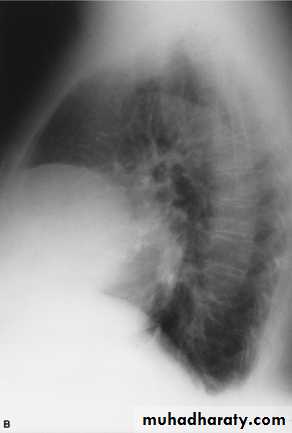

Pneumomediastinum.

Vertical dark (lucent) lines representing air within the mediastinum are usually seen at or above the level of the aortic arch.

On the posteroanterior view (A), these can be seen extending up into the lower cervical soft tissues (arrows).

On the lateral view (B), dark linear air collections can be seen in front of and behind the trachea.